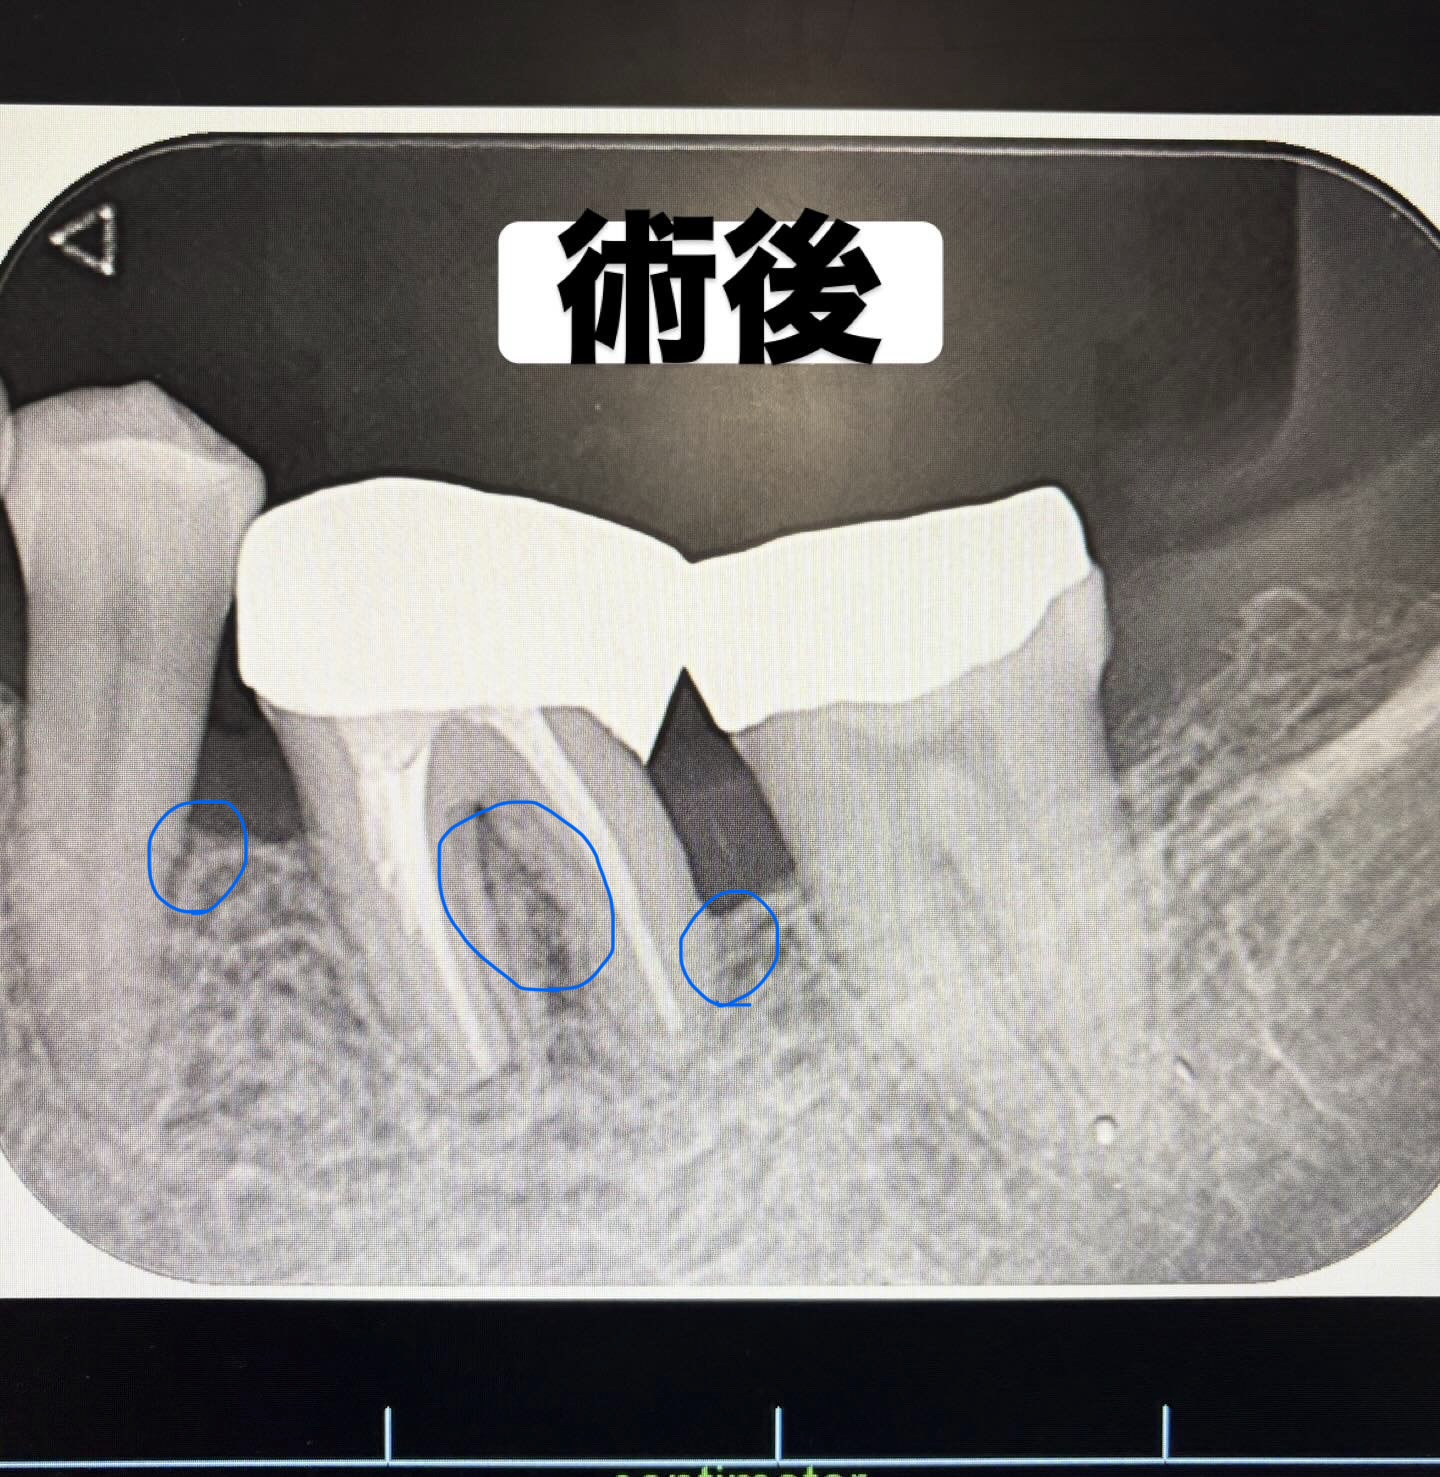

フラップ手術(歯肉剥離掻爬術)とは、中等度から重度に進行した歯周病に対して行われる外科的歯周治療の一つです。歯肉を切開・剥離することで歯根面および歯槽骨を直接明視下に置き、通常の歯周基本治療では除去が困難な深部の歯石や歯周ポケット内の感染組織、炎症性肉芽組織を徹底的に除去します。

この処置により、歯根面を滑沢化し、歯周組織の炎症を抑制するとともに、歯周ポケットの減少や歯周組織の治癒・安定化を図ることが可能となります。フラップ手術は、スケーリング・ルートプレーニングなどの歯周基本治療を十分に行っても改善が認められない症例や、深い歯周ポケットが残存する場合に適応されます。

Before

After

| 主訴 |

歯周病で溶けてしまった歯茎の骨をなんとかしたい |

|---|---|

| 年齢・性別 |

40代・女性 |

| 治療内容 |

歯周再生療法 |

| 治療総額 |

約15万円 |

| 治療期間・回数 |

約半年(週1通院) |

| リスク・副作用 |

当院の歯周再生療法は自費治療のみとなっております。理由として数種類の薬剤をブレンドし、治療効果を向上させているからです。 |